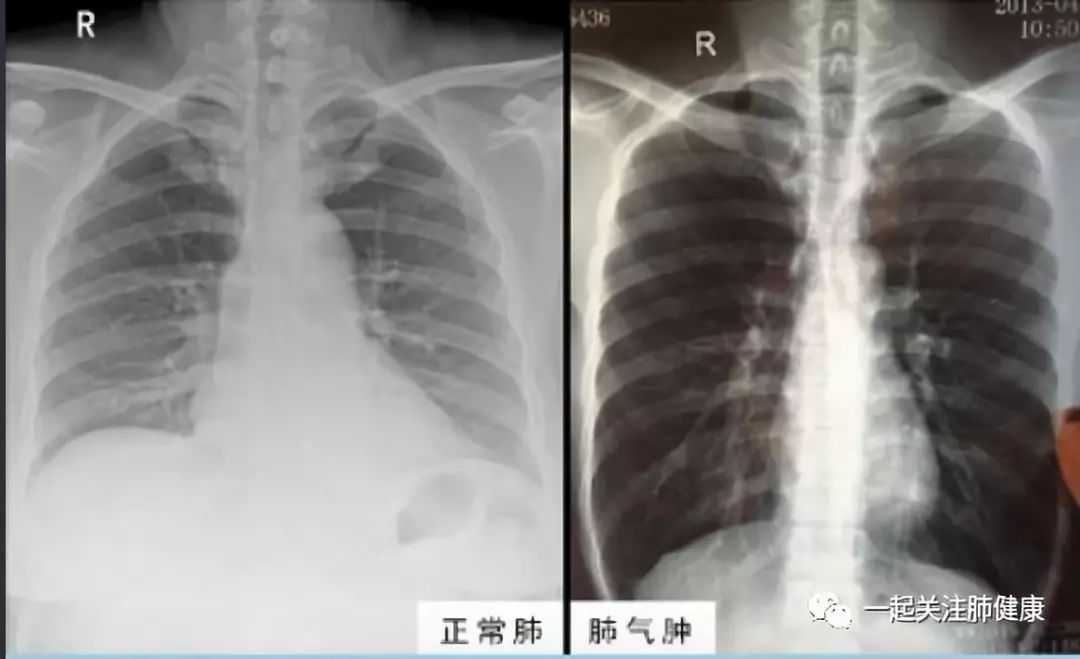

深度剖析慢阻肺之肺气肿和肺心病的病因和治疗

肺气肿和肺癌在症状和临床上大有不同 但还是难以区分

肺气肿目前无法治愈 半数活不过5年 1根蜡烛自测